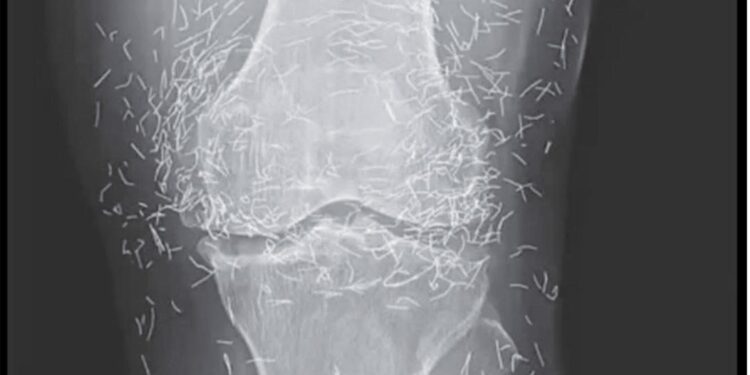

Bei einer routinemäßigen Röntgenuntersuchung entdeckten die Ärzte zu ihrer Überraschung Hunderte kleiner, glänzender Nadeln, die um seine Knie verstreut waren. Eine wahre medizinische Kuriosität, die sowohl Erstaunen als auch Vorsicht weckte. Denn obwohl Gold ein inertes und gut verträgliches Metall ist, ist die längere Anwesenheit von Fremdkörpern im Körper nie ungefährlich.

Laut Experten für medizinische Bildgebung können diese Nadeln bestimmte Körperbereiche auf Röntgenbildern verdecken und so die Diagnose anderer Probleme erschweren. Vor allem erschweren sie die MRT-Untersuchung erheblich: Es besteht die reale Gefahr, dass sich die Nadeln unter dem Einfluss des Magnetfelds bewegen und empfindliches Gewebe schädigen.